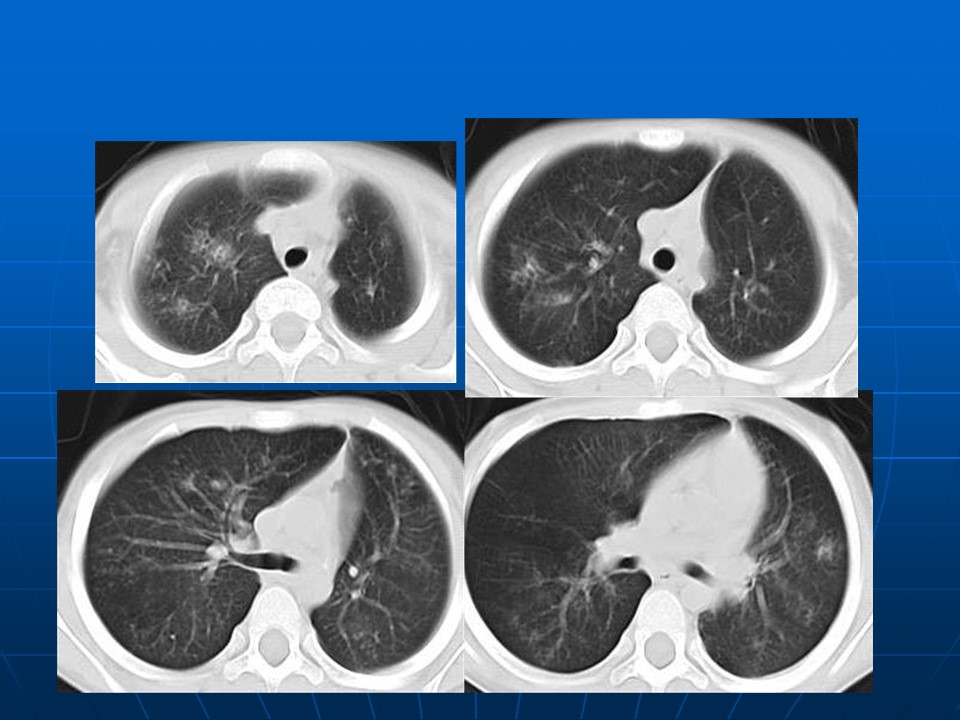

【PPT】肺部炎症新认识点滴